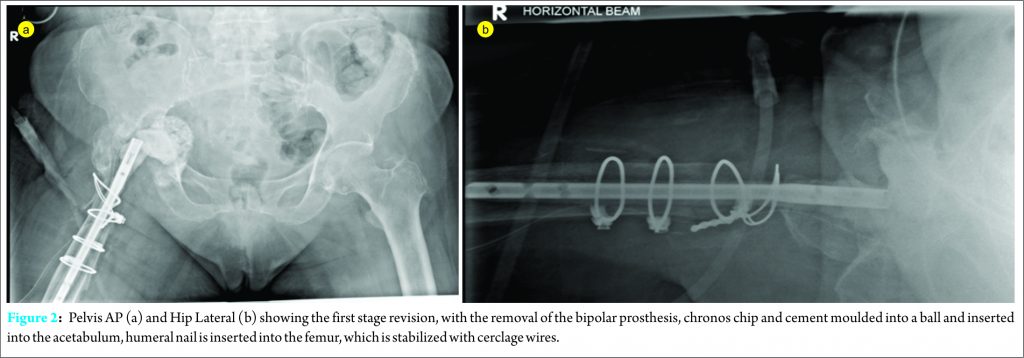

The first stage revision surgery was performed under general anaesthesia in a left lateral position. The old surgical incision via posterior approach was used. Intra-operatively, there was a large amount of fibrotic scar tissue and heterotropic ossification around the proximal femur, with no frank pus or purulent fluid collection. A thick pseudomembrane was present at the base of the protruded bipolar cup. The wires were removed and a proximal, extended trochanteric osteotomy was performed to expose the femoral stem and gain access to the acetabulum. Tissues were sent for cultures and histology. The femoral stem was removed and the superior, anterior edge of the acetabulum was osteotomised to remove the bipolar head. Methylene blue and tobramycin Simplex cement was moulded over a humeral nail and inserted into the femur as a spacer and the femoral fracture was stabilized with cable wires. The pseudomembrane at the acetabulum was covered with chronos chips and cement was moulded into a ball and inserted into the acetabulum. The greater trochanter was then stabilized to the femur and spacer with wires. Post-operative images are shown in Fig. 2(a) and (b).